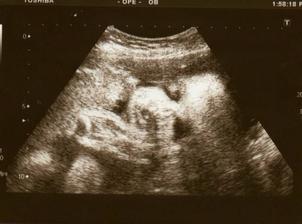

21. 7., 15+4 - mereni nozky, obvodu hrudniku a hlavicky - vse v normalu. Tripple testy, cekame na vysledek...na UTZ byl i tatínek a nejvíce se mu líbilo, jak mimi bije srdíčko. A bude to ... holkaaa🙂

Cas nejak rychle utika, ted me ceka v 30TT velky utz... uz se tesim na materskou, kodrcani do prace je cim dal narocnejsi🙂